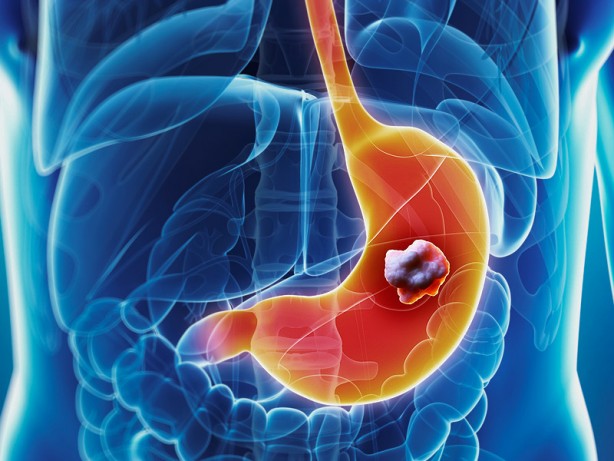

Mide kanseri dünyada kansere bağlı ölümlerde dördüncü sırada yer alıyor. Mide kanseri belirtilerinin başında ise hazımsızlık geliyor.

İHA'ya açıklamalarda bulunan Genel Cerrahi Uzmanı Doç. Dr. Orçun Yalav, mide kanserinin çoğunlukla ilk başlarda hazımsızlık olduğu düşünülen şikayetler sonrasında ortaya çıktığını söyledi.

Yalav, hastalığın başlangıç safhalarında genellikle belirti vermeden ilerleyen bu kanser türünün ülkemizde en sık görülen ilk 5 kanserden birisi olduğunu ve erkeklerde kadınlara göre daha fazla rastlandığını söyledi.